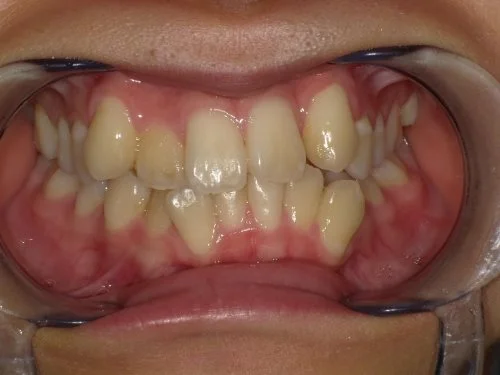

<症例7>歯がガタガタで噛み合わせが悪くお悩み

抜歯無し・マウスピースのみで矯正した症例です。

もともと歯列弓が非常に狭く、V字に近い形をしていたので噛み合わせも非常に不安定でした。

また、下顎前歯部がかなり上の方に生えていたため、下の前歯が上の前歯を突き上げてしまい出っ歯の状態になっていました。

現在では見た目はもちろん、臼歯の噛み合わせも改善しております。

患者様と症状

主訴:歯のガタガタ、噛み合わせが悪い

性別・年齢:20代女性

問題点:叢生(重度)、V字歯列弓、ディープバイト

診断:前歯部の叢生を伴うアングルⅠ級、骨格性Ⅰ級の不正咬合

主なリスク:臼歯の移動に伴い一時的に咬合しにくくなる、歯肉退縮

症状:叢生(そうせい) 過蓋咬合(かがいこうごう)

治療内容

治療期間:1年10ヶ月

治療費用:990,000円(税込)

プラン:Full2プラン

抜歯:無し

再診治療費:無し

追加治療費:無し

保定装置費:無し

治療前後の写真